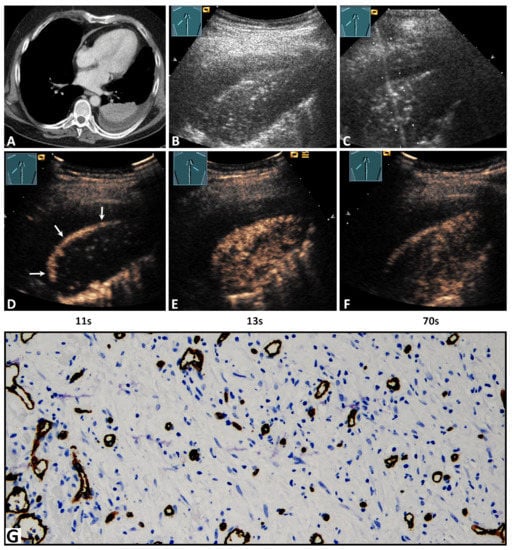

A 62-year-old male patient with lung consolidation on (A) computed tomography (courtesy of Prof. Dr. Andreas H. Mahnken, Department of Radiology, University Hospital Marburg) and (B) B-mode ultrasound. (C) An ultrasound-guided 18G-core needle biopsy of the lung lesion was performed. The histopathological examination of the lesion presented the diagnosis of organizing pneumonia. On contrast-enhanced ultrasound, the lesion showed a delayed enhancement due to (D) a bronchial-arterial supply by peripheral (arrows) bronchial arteries, and (E) a hypoechoic and inhomogeneous pattern of enhancement with (F) an early decrease of enhancement. In the tissue sample, (G) immunohistochemical staining with CD34 was performed, and reorganized lung tissue with fibrotic tissue and a high capillary density in a rather disorganized and chaotic pattern was present, consistent with pattern B (×200).

Regarding TE, 27/38 lesions (71.1%) revealed a delayed enhancement due to BA perfusion (Figure 2D), and 11/38 lesions (28.9%) revealed an early enhancement due to PA perfusion (Figure 3D). Regarding EE, 29/38 cases (76.3%) revealed a marked enhancement (Figure 3E) and 9/38 cases (23.7%) a reduced enhancement (Figure 2E). Furthermore, 7/38 lesions (28.4%) showed a homogeneous arterial enhancement (Figure 3E), and 31/38 lesions (81.6%) showed an inhomogeneous arterial enhancement with evidence of NPAs on CEUS (Figure 2E). The DE (washout time) was rapid (<120 s) in 19/38 lesions (50.0%) and late (≥120 s) in 19/38 lesions (50.0%) (Figure 2F and Figure 3F).

3.4. Histopathological Data and Their Correlation with Contrast-Enhanced Ultrasound Pattern

All POPs were histologically confirmed to exclude malignancy. The histological confirmation was performed by ultrasound-guided biopsy in 25 cases (65.8%) (Figure 2C and Figure 3C) and by a thoracic surgical intervention in 13 cases (34.2%). The mean time difference between CEUS and histopathological sampling was 1.8 ± 1 weeks (range 1–4 weeks). A vascular pattern B similar to BA neoangiogenesis in lung tumors was found in all lesions (Figure 2G and Figure 3G). Moreover, in the 11/38 lung lesions (28.9%) that had a PA pattern of enhancement, the vascular pattern A similar to PA supply in healthy lung tissue [] or acute pneumonia [] was identified in addition to vascular pattern B (Figure 3G).

On immunohistochemical staining with CD34 antibody, avascular areas (abscess, necrosis, hemorrhage) in POP were identified in 13/31 cases (41.9%) with an inhomogeneous enhancement on CEUS.

Regarding TE in this study, on CEUS, POPs had a predominantly (71.1%) delayed systemic enhancement in the arterial phase, indicating a BA supply. In all tissue samples, a disorganized and chaotic vascular pattern was seen (Figure 2) as evidence of BA neoangiogenesis [,]. Furthermore, in all lesions with a PA perfusion pattern of enhancement (28.9%), a regular alveolar vascular pattern was partially present in the corresponding tissue sample as an indication of PA supply (Figure 3) []. These findings indicate that, in the presence of a PA pattern of enhancement, a BA neoangiogenesis, as an important feature of chronic inflammatory and malignant processes, cannot be excluded by CEUS. In these lesions, early PA enhancement covered the delayed arrival of contrast medium via BA supply.

Regarding HE and EE, 81.6% of cases presented an inhomogeneous enhancement and 76.3% a marked arterial enhancement in comparison with splenic enhancement. Avascular areas (abscess, necrosis, hemorrhage), as a histopathological correlation to an inhomogeneous enhancement, were identified in 13/31 cases (41.9%). In the remaining cases, a histopathological correlation was not demonstrated, based on the fact that avital tissues were avoided in the biopsy or histopathological examination. All POPs with a PA pattern of enhancement showed a marked enhancement similar to other pathologies with PA supply, such as compression atelectasis and acute pneumonias [,,]. Furthermore, 18/27 lesions (66.7%) with a BA pattern of enhancement showed an isoenhancement that may be indicative of a marked neoangiogenesis [].

Regarding DE, 50% of POPs revealed a rapid decrease of enhancement (<120s) in the parenchymal phase. Furthermore, it was demonstrated that the presence of late DE (>120s), as a further feature of benign pulmonary lesions [], did not also exclude a BA neoangiogenesis.